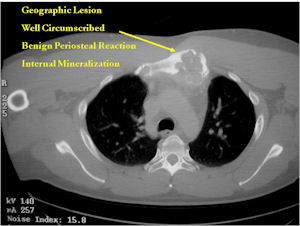

Plain X-rays:

- Geographic, circumscribed lesion usually around 5cm in size.

- There may be expansion of bone, cortical thinning and cortical breakthrough. A soft tissue mass may accompany this lesion but the soft tissue component is usually contained by the periosteum.

- The periosteum remains intact around the soft tissue component. Might need a CT scan to detect the subtle calcification (Egg Shell Rim of Calcification) associated with an intact periosteal reaction

- The lesion may be entirely radiolucent but usually shows some degree of mineralization. Mineralization may appear stippled like cartilage but do not see chondroid pathologically. Mineralization is sometimes better detected on a CT scan rather than an x-ray.

CT Scan:

- More useful for detecting mineralization and evaluating extent of bone destruction than plain X-ray

MRI:

- Also useful in determining extent

- There is often extensive edema around the tumor in the surrounding bone and soft tissues that can lead to a misdiagnosis of a malignant tumor.